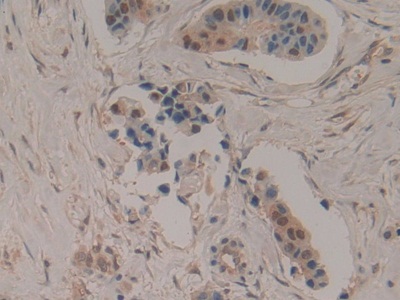

Polyclonal Antibody to Superoxide Dismutase Copper Chaperone (PAA596Hu01)

| Валидировано для | IHC WB Иммуногистохимия; Вестерн-блоттинг |

| Рекомендуемые разведения | WB: 0.01-2 мкг/мл; IHC: 5-20 мкг/мл; Оптимальное разведение определяется конечным потребителем |